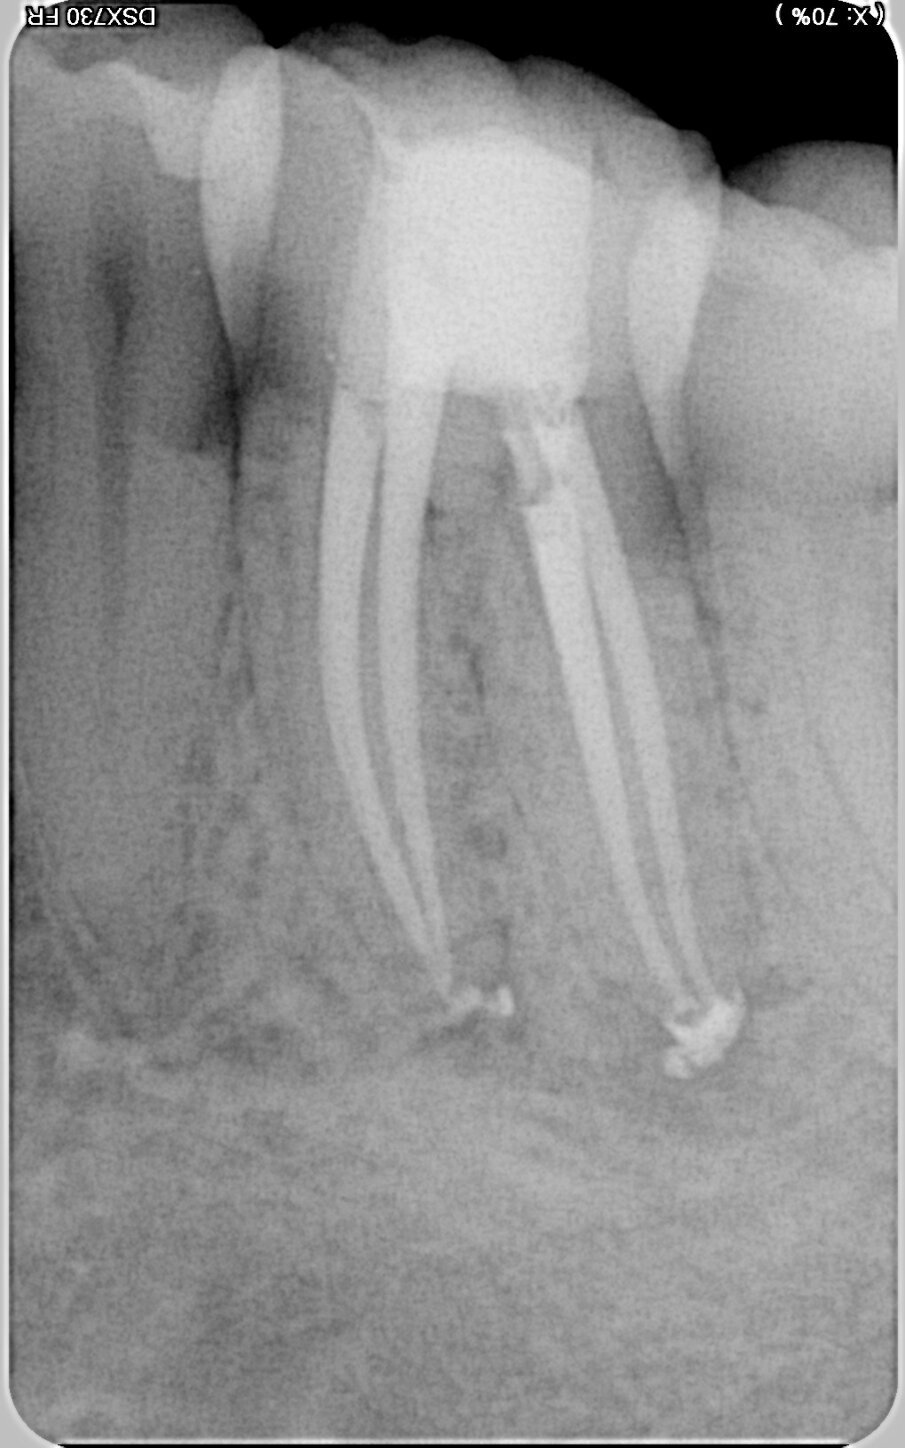

In Case 1, the appropriate access was achieved with an orifice opener. The extreme curvature in the apical third presented a particular challenge during preparation. The following sequence was therefore used: the 10/.05 HyFlex EDM file was followed by the 20/.05, and the universal file 25/~ HyFlex EDM OneFile then performed most of the work in the mesial and distal root canals. The final sequence involved the 40/.05, 50/.03 and 60/.02 files in the distal root canals for final shaping. In this process, Jeni enabled rapid preparation despite the highly curved profile of the root canals. Each file virtually worked itself to its working length. The natural shaping of the root canals is clearly shown in the postoperative radiographic image (Fig. 3).